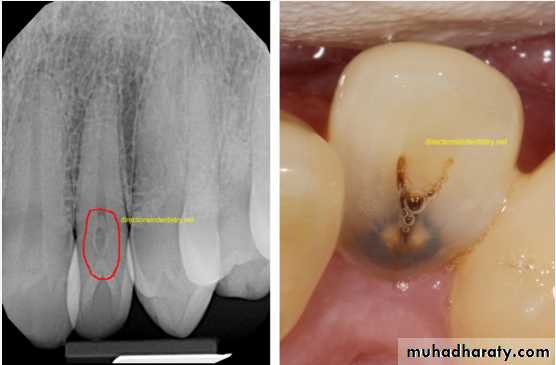

Dens in Dente (invaginated odontome) :

*It is an infolding of the outer surface of a tooth into the interior usually in the cingulum pit region of maxillary lateral incisors (tooth within a tooth).

*It is of 2 forms:coronal& radicular.

*Clinicaly varies from slight enlargement of cingulum

to a deep infolding that extends to the apex.

It has been classified into 3 major types:

*Type I:it is confined within the crown of the tooth and does not extend beyond the level of the external CEJ. *Type II :extends below CEJ ends in a blind sac, may or may not communicate with adjacent dental pulp. *Type III:extends through the root and communicates laterally with the periodontal ligament space through a pseudo-foramen or at the apical foramen . There is usually no communication with the pulp, which lies compressed within the root.*Most cases of dens in dente are discovered radiographically. It is more radiopaque than the surrounding tooth structure and can easily be identified.